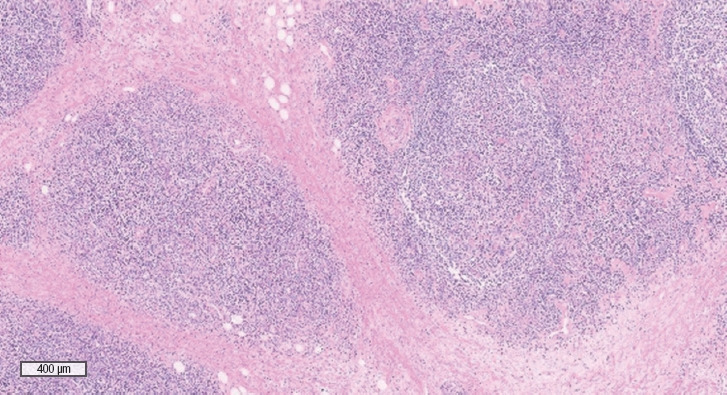

嗜酸性粒细胞增多性血管淋巴样增生症(ALHE)是一种罕见的疾病,主要表现为头颈部结节性病变,常引起不适或疼痛。由于其罕见性和缺乏既定的指南,治疗仍然具有挑战性。本报告介绍了一例影响耳垂的 ALHE 病例,该病例通过耳小叶缩小手术和随后的区域内类固醇注射成功治愈。一名 31 岁的女性患者曾反复出现耳垂肿块,为避免失去耳垂,她接受了部分切除手术。组织病理学检查确诊为木村病,这是 ALHE 的一种变异型。随后进行的局部甲基强的松龙注射有效控制了残余病灶,使病灶明显缩小,但未出现凹痕。针对这种疾病,人们尝试了各种治疗方法,但复发率仍然很高。手术切除结合皮质类固醇内注射是首选方法。在这个病例中,我们采用了颞下沟技术进行耳垂缩小,以保留耳小叶的外侧边缘,将畸形风险降至最低,并获得可预测的结果。颞沟下技术提供了一种在不影响美观的情况下缩小耳垂的方法。要阐明 ALHE 的发病机制,并为这种罕见病制定标准化治疗方案,还需要进一步的研究。

Angiolymphoid hyperplasia with eosinophilia (ALHE) is a rare condition characterized by nodular lesions predominantly in the head and neck region, often causing discomfort or pain. Treatment remains challenging because of its rarity and the lack of established guidelines. This report presents a case of ALHE affecting the earlobes that was successfully managed using ear lobule reduction surgery and subsequent intralesional steroid injections. A 31-year-old woman with a history of recurrent earlobe masses underwent a partial excision to avoid the loss of the earlobe. Histopathological examination confirmed Kimura disease, a variant of ALHE. Subsequent local methylprednisolone injections effectively controlled the remaining lesions, resulting in significant size reduction without notching. Various treatment modalities have been attempted for this condition; however, recurrence rates remain high. Surgical resection combined with intralesional corticosteroid injections is the preferred approach. In this case, a sub-antitragal groove technique for earlobe reduction was employed to preserve the lateral edge of the ear lobule, minimize the risk of deformity, and achieve a predictable outcome. The sub-antitragal groove technique offers an approach to reduce earlobe size without compromising aesthetics. Further research is required to elucidate the pathogenesis of ALHE and establish standardized treatment protocols for this rare condition.